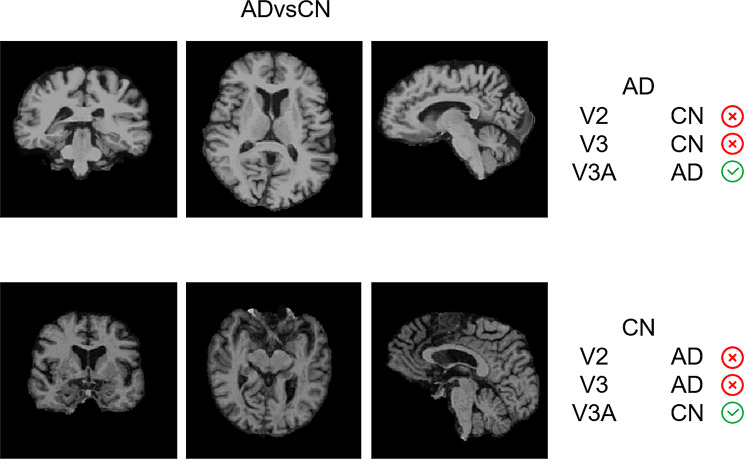

Early diagnosis of Alzheimer's disease (AD) and its precursor, mild cognitive impairment (MCI), is critical for effective prevention and treatment. Computer-aided diagnosis using magnetic resonance imaging (MRI) provides a cost-effective and objective approach. However, existing methods often segment 3D MRI images into 2D slices, leading to spatial information loss and reduced diagnostic accuracy. To overcome this limitation, we propose TA-SSM Net, a deep learning model that leverages tri-directional attention and structured state-space model (SSM) for improved MRI-based diagnosis of AD and MCI. The tri-directional attention mechanism captures spatial and contextual information from forward, backward, and vertical directions in 3D MRI images, enabling effective feature fusion. Additionally, gradient checkpointing is applied within the SSM to enhance processing efficiency, allowing the model to handle whole-brain scans while preserving spatial correlations. To evaluate our method, we construct a dataset from the Alzheimer's Disease Neuroimaging Initiative (ADNI), consisting of 300 AD patients, 400 MCI patients, and 400 normal controls. TA-SSM Net achieved an accuracy of 90.24% for MCI detection and 95.83% for AD detection. The results demonstrate that our approach not only improves classification accuracy but also enhances processing efficiency and maintains spatial correlations, offering a promising solution for the diagnosis of Alzheimer's disease.